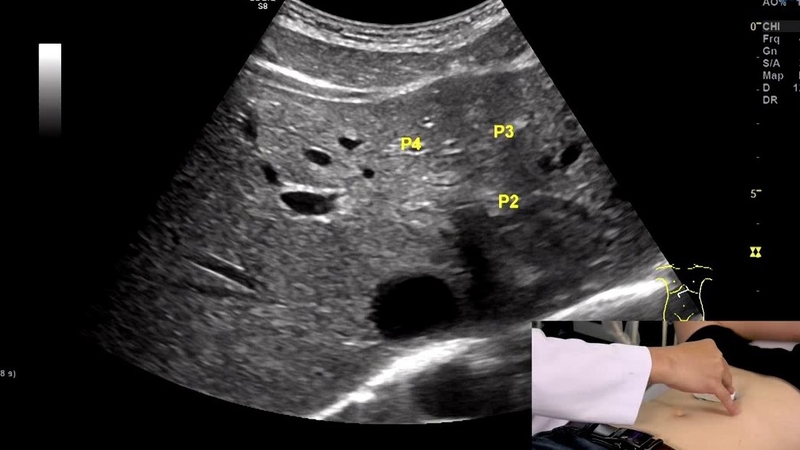

Trong lĩnh vực siêu âm, echo là thuật ngữ mô tả âm thanh được phản xạ lại từ các cơ quan và mô trong cơ thể khi sóng siêu âm từ máy quét đi qua. Quá trình phản xạ này tạo ra những điểm ánh sáng trên hình ảnh siêu âm, được gọi là các khối echo.

Các khối echo cung cấp thông tin quan trọng về cấu trúc, kích thước và bề mặt của các bộ phận trong cơ thể. Chúng được sử dụng để đánh giá sức khỏe của bệnh nhân thông qua việc phân tích hình ảnh siêu âm. Ví dụ, trong siêu âm thận, các khối echo có thể cho thấy kích thước, hình dạng và cấu trúc bên trong của thận, cũng như phát hiện các vấn đề sức khỏe như sỏi thận hay là các khối u.

Sử dụng khối echo trong siêu âm mang lại nhiều lợi ích. Đầu tiên, nó giúp phát hiện và chẩn đoán các bệnh lý như khối u, sỏi thận và nhiễm khuẩn. Thứ hai, nó cho phép tạo ra hình ảnh chi tiết và chính xác thông qua điều chỉnh độ sâu và góc quét. Cuối cùng, khối echo cung cấp thông tin về cấu trúc, tính chất của các cơ quan và mô, hỗ trợ trong quá trình chẩn đoán và theo dõi điều trị.

Sự phản xạ của sóng siêu âm từ khối echo cho thấy sự khác biệt về mức độ hấp thụ và phản xạ của các vật chất trong cơ thể như mô mềm, mô cứng, các chất lỏng, hoặc là các khối u. Điều này cho phép các chuyên gia y tế nhìn thấy, nhận biết và đánh giá sự tồn tại của các vật chất này trên hình ảnh siêu âm.

Việc sử dụng khối echo trong kỹ thuật siêu âm mang lại nhiều lợi ích quan trọng. Đầu tiên, nó giúp trong việc phát hiện và chẩn đoán các vấn đề và bệnh lý trong cơ thể như khối u, sỏi thận, nhiễm khuẩn, hoặc tổn thương mô mềm. Bên cạnh đó, nó cho phép điều chỉnh độ sâu cũng như góc quét để tạo ra hình ảnh chi tiết và chính xác. Cuối cùng, khối echo cung cấp thông tin về cấu trúc và tính chất của các cơ quan và mô, hỗ trợ trong quá trình chẩn đoán và giám sát điều trị.